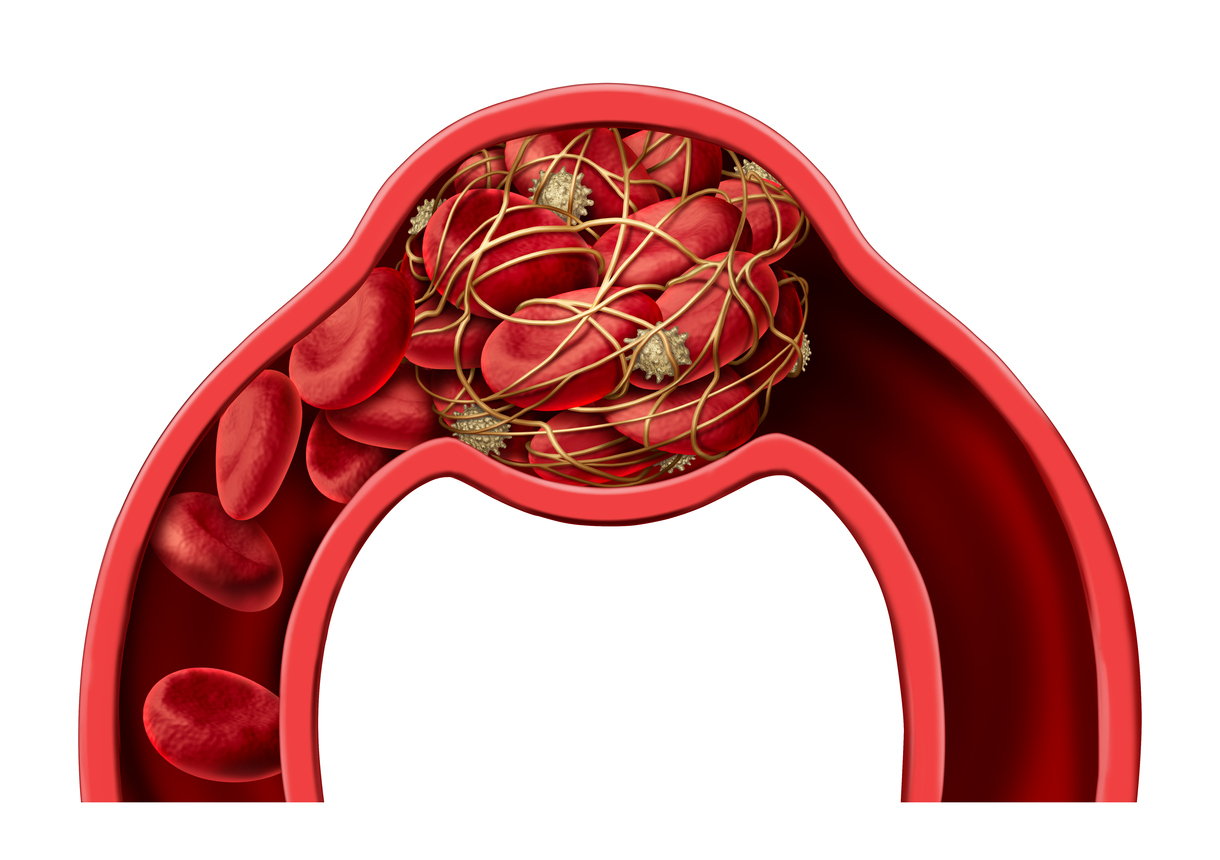

:max_bytes(150000):strip_icc()/overview-blood-clots-1745326_final-3990f6d12e19428e8734d92f068ce0de.png)

:max_bytes(150000):strip_icc()/overview-blood-clots-1745326_final-3990f6d12e19428e8734d92f068ce0de.png)